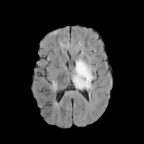

Qualitative Results. Figure 3 showcases StegoGAN’s qualitative performance against other image translation algorithms. Notably, StegoGAN effectively avoids generating unmatchable classes such as texts, highways, and tumors, while producing high-quality image translations.

Quantitative Results. On the PlanIGN dataset (Table 1) and the Brats MRI dataset (Table 2), StegoGAN outperforms others in fidelity, achieving the lowest RMSE by a margin of on PlanIGN and by for Brats MRI. Furthermore, it significantly enhances pixel accuracy, with improvements of in Acc() and in Acc() on PlanIGN. In the MRI dataset, StegoGAN dramatically reduces false positive rates—–over 20 lower than CycleGAN and 10 less than the next best model SRUNIT (for pFPR).

We label each scan as tumorous if more than of its pixels are labelled as such, and as healthy if it contains no tumor pixels. We only use high-grade gliomas (HGG) instead of low-grade gliomas (LGG) as the are more easily observable [24]. In total, we obtain 5035 pathological pairs and 1135 healthy pairs. The train set is composed of a source domain of T1 images of healthy brains, while the target domain set is composed of FLAIR scans of which (60%) are tumorous and healthy. The test set is composed of aligned scans of healthy brains in both modalities.